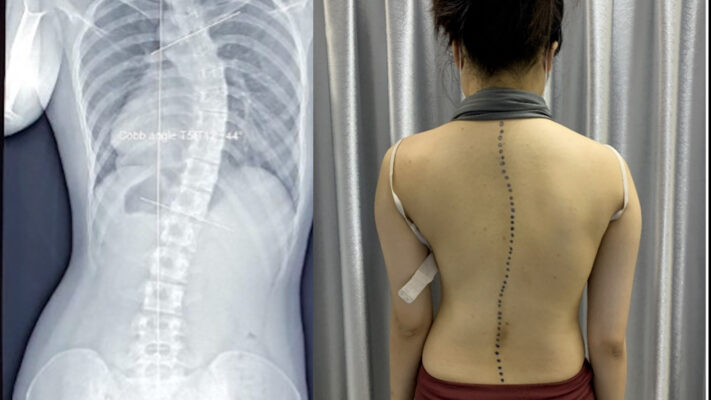

Cột sống lưng bị cong hay còn gọi là vẹo cột sống, là tình trạng cột sống có đường cong bất thường theo chiều ngang hoặc xoắn. Thay vì một đường thẳng khi nhìn từ phía sau, cột sống có hình dạng chữ C hoặc chữ S. Cột sống lưng bị cong là một vấn đề sức khỏe ngày càng phổ biến trong xã hội hiện đại. Tình trạng này không chỉ ảnh hưởng đến ngoại hình mà còn gây ra nhiều biến chứng nghiêm trọng nếu không được phát hiện và điều trị kịp thời.

Một trong những dấu hiệu dễ nhận thấy nhất là sự không cân đối của vai và hông: Người bị cong vẹo cột sống thường có một bên vai cao hơn bên kia, hoặc một bên hông nhô ra nhiều hơn. Ngoài ra, khi quan sát từ phía sau, có thể thấy một bên xương bả vai nhô cao hơn, và thân mình có xu hướng nghiêng sang một bên.

- Vẹo cột sống hình chữ C là dạng cong đơn giản nhất, trong đó cột sống cong sang một bên tạo thành hình chữ C.

- Phức tạp hơn là vẹo cột sống hình chữ S, khi cột sống có hai đường cong ngược chiều nhau. Ngoài ra còn có tình trạng gù lưng (Kyphosis), khi phần trên của cột sống cong ra phía sau quá mức, và ưỡn cột sống (Lordosis), khi phần dưới của cột sống cong về phía trước quá nhiều.